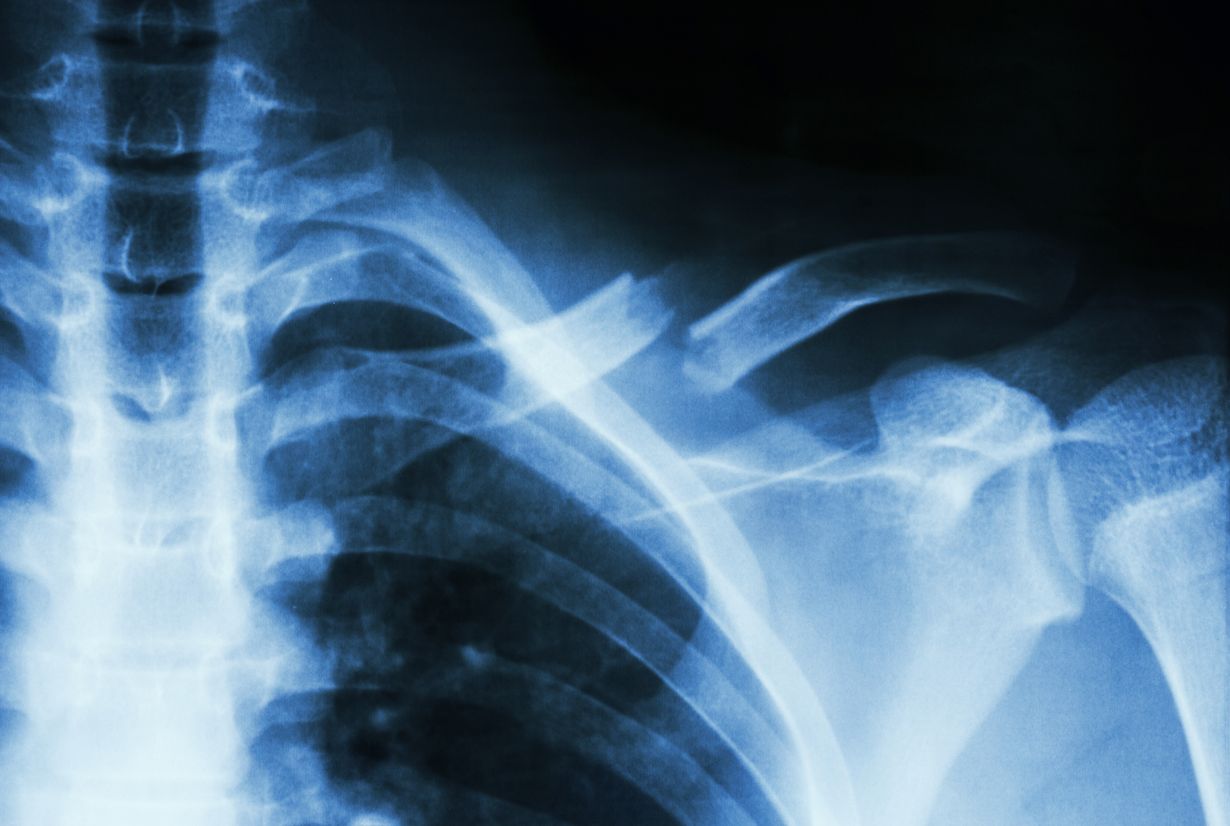

Laske luidesi murtumariski helposti

Nyt voit arvioida itse murtumariskisi. Se onnistuu vaivattomasti kätevällä murtumariskilaskurilla.

Murtumariskilaskuri arvioi osteoporoottisen murtumariskin. Laskuri on tehty nimenomaan ikääntyvän väestön murtumariskin arvioimiseksi, sekä suuren yleisön että lääkäreiden työkaluksi.